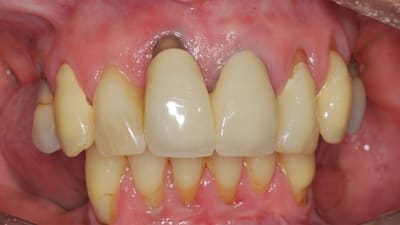

Case Reports Oral Surgery Implantology Ridge Augmentation in a Site of a Previous Implant Failure Using Tenting Screws With Allograft and Collagen Membrane By Daniela Gurpegui Abud, DDS, Dennis P. Tarnow, DDS, Jaffer A. Shariff, DDS March 01, 2022 15 min read